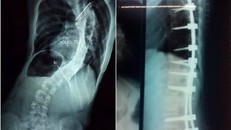

Cột sống bệnh nhi cong vẹo trước mổ (bên trái) và được nắn chỉnh sau mổ

Phẫu thuật thành công bé gái vẹo cột sống ngực 111 độ kèm dị tật tủy sống

25/12/2017 18:00

(Ngày Nay) - Bác sĩ Nguyễn Hoàng Trung, Bệnh viện Chấn thương Chỉnh hình TP HCM cho biết, đây là một ca rất nặng. Góc vẹo tại đoạn cong chính của cột sống lên đến 111 độ, kèm theo dị tật trong tủy sống cổ là bệnh rỗng tủy.